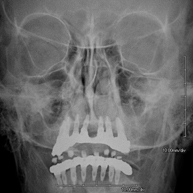

- Paranasal Sinuses X-ray

This technique uses X-ray rendered imaging for examining the paranasal sinuses. Indicated for: difficulty breathing through the nose, chronic cough, headache, mucus.